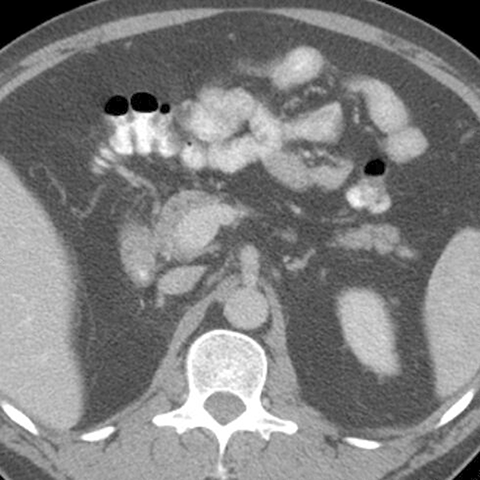

Normal Pancreas, Axial CT [3 of 5]